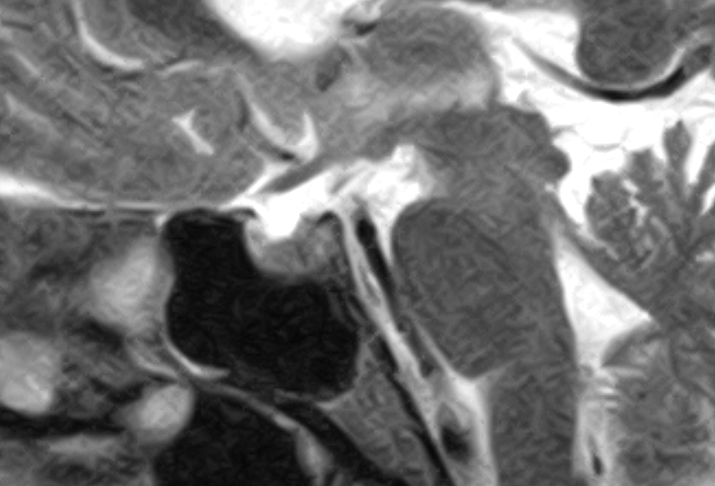

The patient was sent for thorough investigations and MRI cervical spine performed 04-September-2016 showed huge meningioma 33x12.7 mm intradurally pushing the spinal cord to the left. Spectroscopy was typical for meningioma and the mass was lacking fibers. There was and extension to the right C1-2 foramen reaching the vertebral artery pushing it anterior.

In prone position with the use of IOM ISIS, laminectomy of C2-3 and partial of C1 was achieved. The dura was opened slightly right parallel to the midline. The dumbbell-shaped appearance of the tumor was due to right C2 anterior and posterior rootlets, which were constricting the tumor and they were preserved to the end of surgery. The matrix of the meningioma was the right lateral wall of the dura, which was coagulated and piece-meal resection of the tumor was performed. MEP was troubleshooting and not informative. After the resection of the tumor a tiny piece and the emergence of the right C1 was removed trying during that to preserve the rootlets. Using MultiGen, bipolar motor stimulation of right C2 was achieved with 1.0 V. Motor stimulation of the right side of the spinal cord and a brisk response of the right upper and lower limbs was achieved above the tumor resection area. Irrigation of the area with 1 ampoule Papaverine diluted with 20 ml saline. The dura was closed water-tightly. Routine closure of the wound. The patient was sent to MRI before extubation.

Fig-17: Anatomical architecture of the spinal cord at C2-C3 level.